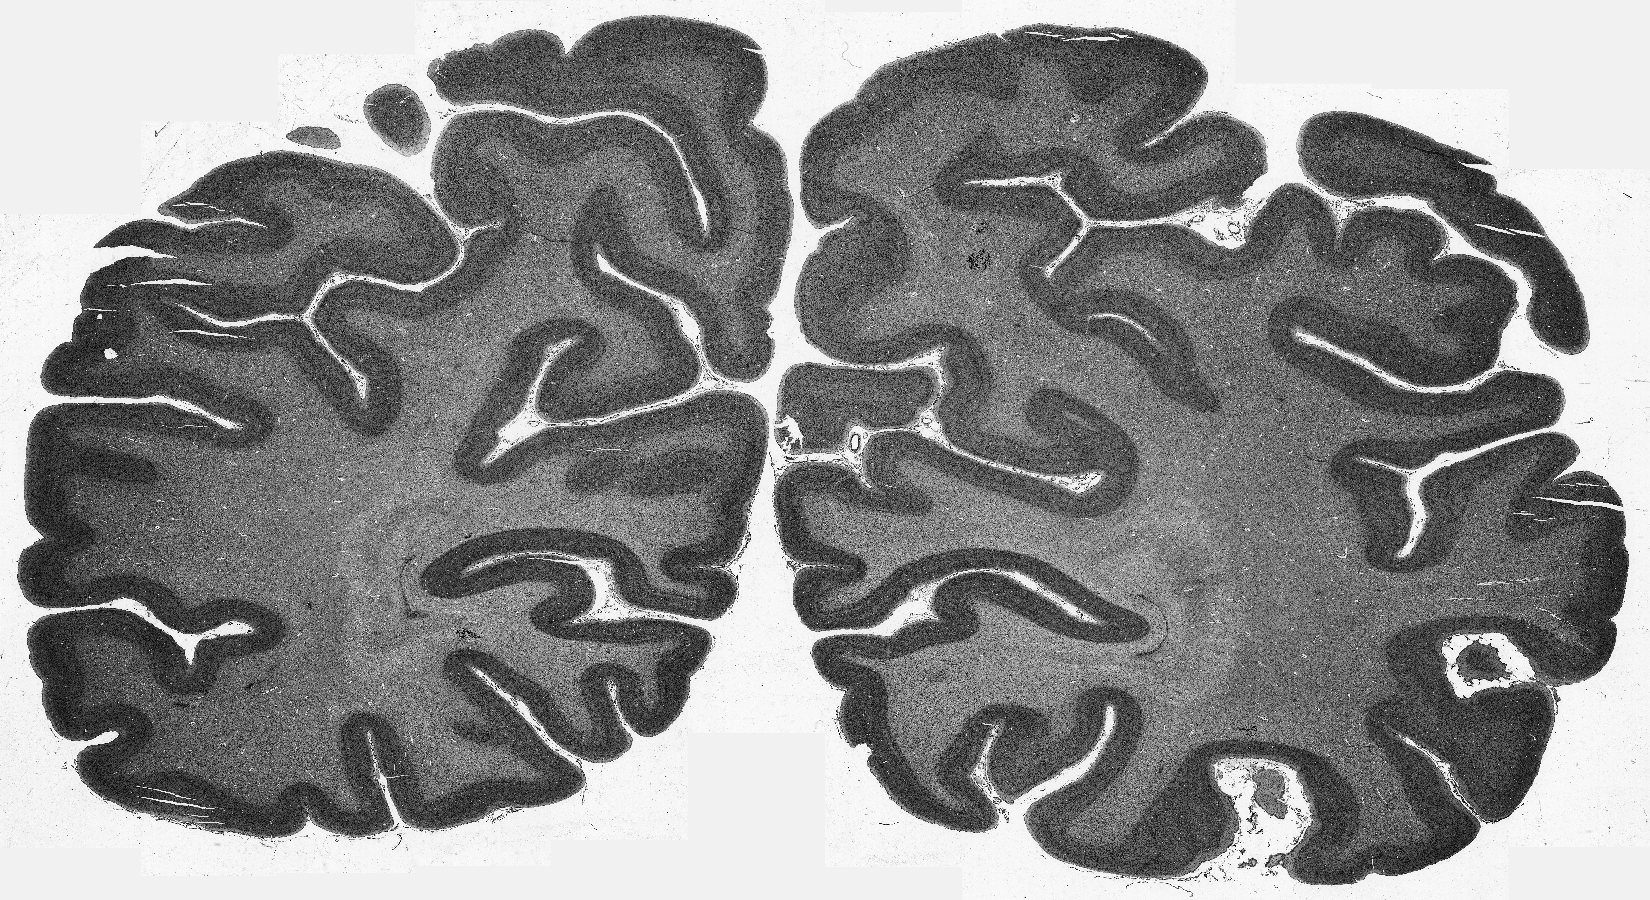

Cytoarchitectonic maps provide microstructural reference parcellations of the brain, describing its organization in terms of the spatial arrangement of neuronal cell bodies as measured from histological tissue sections. Recent work provided the first automatic segmentations of cytoarchitectonic areas in the visual system using Convolutional Neural Networks. We aim to extend this approach to become applicable to a wider range of brain areas, envisioning a solution for mapping the complete human brain. Inspired by recent success in image classification, we propose a contrastive learning objective for encoding microscopic image patches into robust microstructural features, which are efficient for cytoarchitectonic area classification. We show that a model pre-trained using this learning task outperforms a model trained from scratch, as well as a model pre-trained on a recently proposed auxiliary task. We perform cluster analysis in the feature space to show that the learned representations form anatomically meaningful groups.